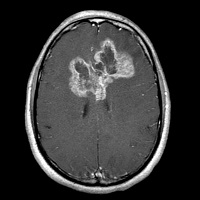

опухоль бабочка головного мозга

Смертельная «бабочка» глиобластомы попалась в сети лазера

Эту проблему необходимо было срочно решать, так как ЛИТТ впервые давала надежду пациентам с большими и/или сложными опухолями, например, глиомой в виде бабочки. В процессе попыток избавиться от отёка обнаружилось, что «сваренная» опухоль не плотная, а мягкая и рыхлая. Поскольку снабжающие ее сосуды тоже «запекаются» под действием лазера, такую опухоль можно относительно безопасно аспирировать с помощью специального отсоса через то самое крошечное отверстие в черепе. В публикации рассматриваются результаты лечения 10 пациентов с труднодоступными злокачественными опухолями мозга средним объемом 38 см3. У восьми была глиобластома, в том числе в форме бабочки, один пациент с глиобластомой уже прошел курс терапии, а у одного был метастаз меланомы в мозге.